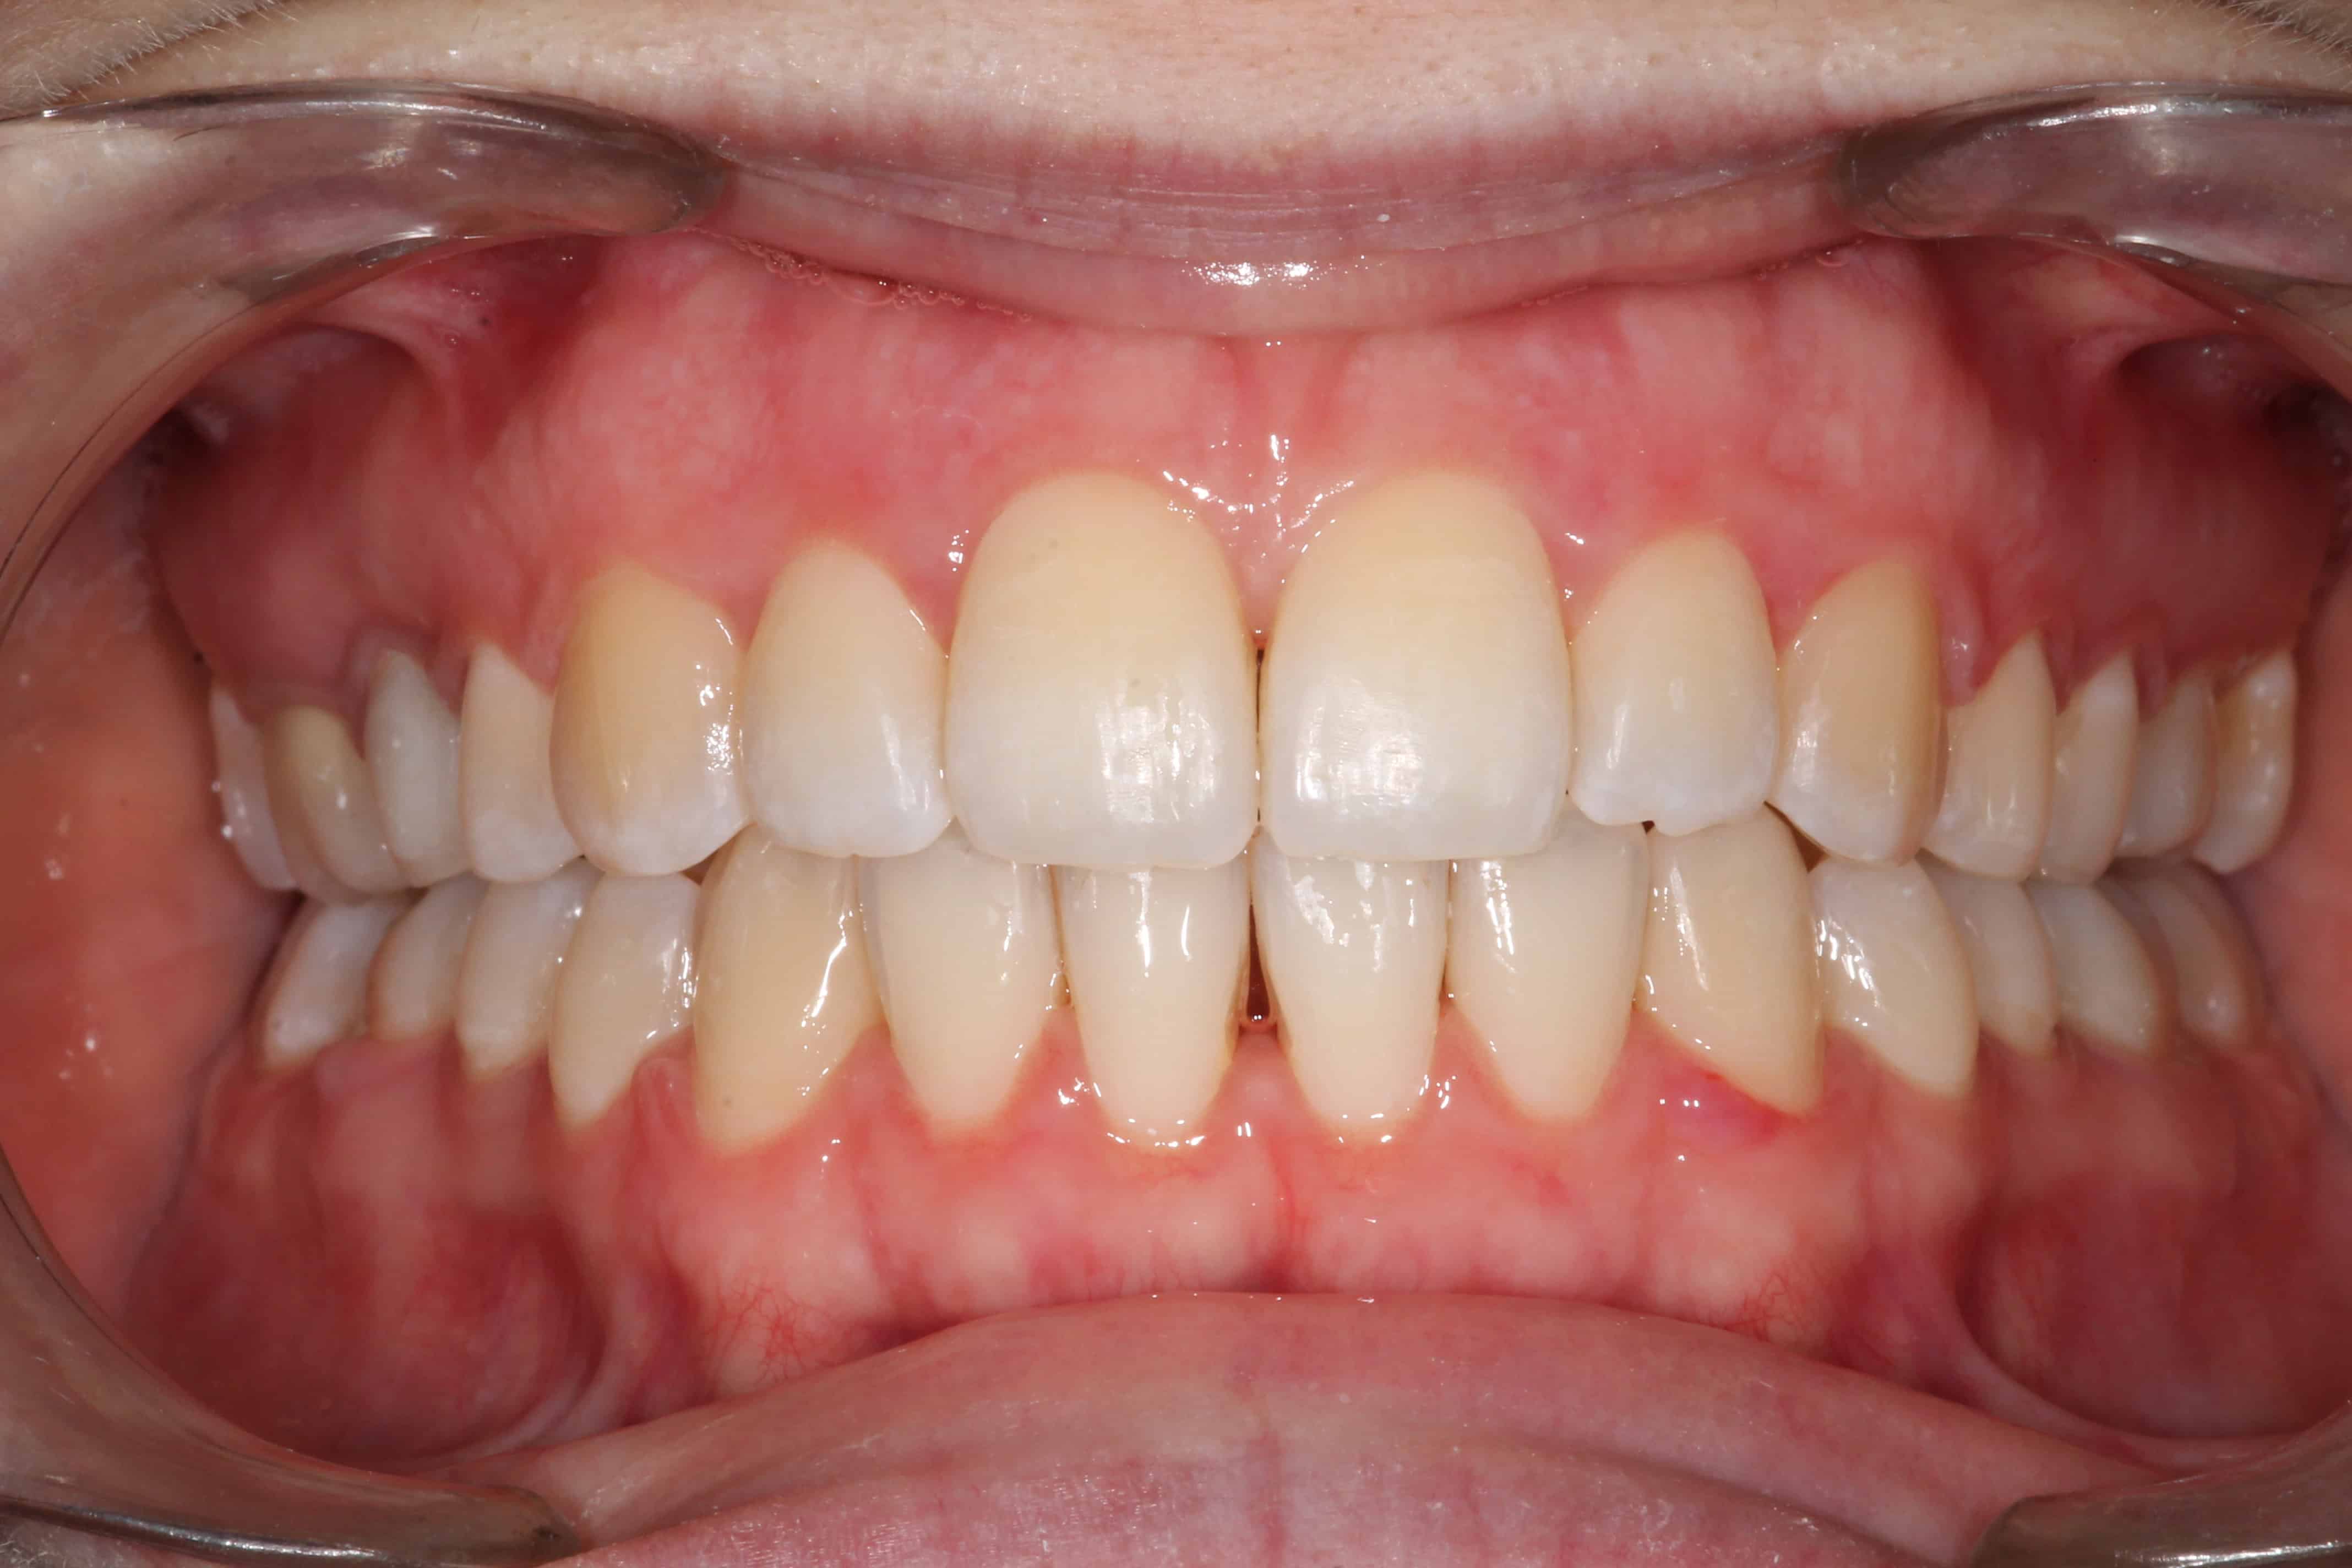

Exemple de cas :